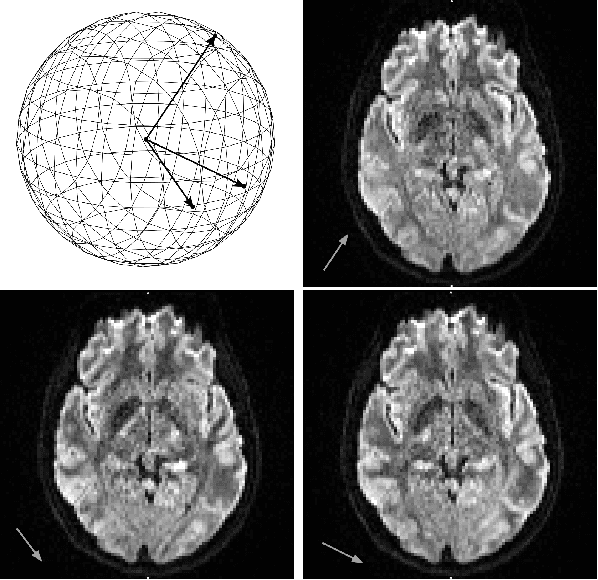

Abstract:Diffusion MRI is a modern neuroimaging modality with a unique ability to acquire microstructural information by measuring water self-diffusion at the voxel level. However, it generates huge amounts of data, resulting from a large number of repeated 3D scans. Each volume samples a location in q-space, indicating the direction and strength of a diffusion sensitizing gradient during the measurement. This captures detailed information about the self-diffusion, and the tissue microstructure that restricts it. Lossless compression with GZIP is widely used to reduce the memory requirements. We introduce a novel lossless codec for diffusion MRI data. It reduces file sizes by more than 30% compared to GZIP, and also beats lossless codecs from the JPEG family. Our codec builds on recent work on lossless PDE-based compression of 3D medical images, but additionally exploits smoothness in q-space. We demonstrate that, compared to using only image space PDEs, q-space PDEs further improve compression rates. Moreover, implementing them with Finite Element Methods and a custom acceleration significantly reduces computational expense. Finally, we show that our codec clearly benefits from integrating subject motion correction, and slightly from optimizing the order in which the 3D volumes are coded.

Abstract:Edge-enhancing diffusion (EED) can reconstruct a close approximation of an original image from a small subset of its pixels. This makes it an attractive foundation for PDE based image compression. In this work, we generalize second-order EED to a fourth-order counterpart. It involves a fourth-order diffusion tensor that is constructed from the regularized image gradient in a similar way as in traditional second-order EED, permitting diffusion along edges, while applying a non-linear diffusivity function across them. We show that our fourth-order diffusion tensor formalism provides a unifying framework for all previous anisotropic fourth-order diffusion based methods, and that it provides additional flexibility. We achieve an efficient implementation using a fast semi-iterative scheme. Experimental results on natural and medical images suggest that our novel fourth-order method produces more accurate reconstructions compared to the existing second-order EED.